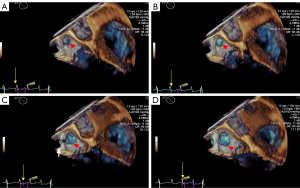

The LAA (Figure 2A,B,C,D, red arrowhead) can be seen in varying sizes during the different phases of the cardiac cycle (the yellow arrow points to the time frame of the cycle). As demonstrated in Figure 2, patients with long-standing AFib showed a different contraction and relaxation LAA morphology during AFib, noting that a coumadin ridge was found in the same patient (Figure 2, asterisk). LAA morphology parameters, including depth, orifice diameter, and orifice area should be strictly assessed in the same cardiac cycle. In order to discover more LAA details and differences between the two AFib classifications, these LAA morphology parameters were further collected and compared by RT-3D TEE. We found that the LAA orifice was markedly enlarged in long-standing patients, compared with paroxysmal AFib group (Figure 3, Table 3). The diameter of the LAA orifice was carefully measured from multiple angles, including the 45° and 135° views. The average systolic inner diameter of the LAA opening in the 135° view were 23.9±8.4 and 28.7±7.6 mm, in the paroxysmal and long-standing groups, respectively (P=0.03). The average diastolic inner diameter of the LAA opening in the 135° view were 19.3±8.9 and 24.0±10.1 mm in paroxysmal and long-standing groups, respectively (P=0.04). Meanwhile, there was no difference in terms of the LAA orifice diameter in the 45° view (P=0.05 in systole, P=0.13 in diastole). Long-standing AFib group patients also had a markedly greater value of LAA area in the systolic and diastolic phases compared with the paroxysmal group (P=0.01). However, the LAA depth did not differ significantly between them (30.2±13.6 vs. 32.4±15.8, respectively, P=0.43) (Table 3).